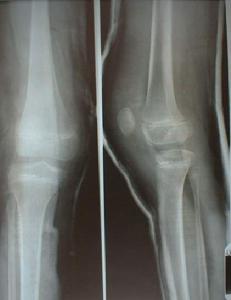

出生後即見一側或雙側的膝關節屈曲攣縮,不能伸直,髕骨已移至股骨髁的外側,不能主動伸膝,被動伸膝也受限。由於髕骨較小,且不能伸膝,故在嬰兒的股骨髁外側不易捫及髕骨。2歲以前的X線側位片上可見伸膝裝置的陰影消失。2歲以後髕骨骨化中心逐漸出現,正位片上可見髕骨位於股骨髁的外側。